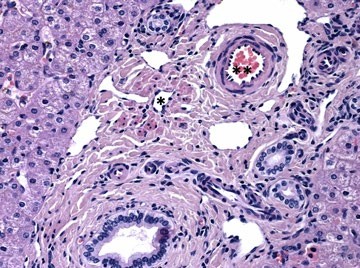

• Histopathological Atlas of Vascular Liver Disorders

Fátima Carneiro, Christine Sempoux

60-64

DOI: https://doi.org/10.60591/crspmi.571